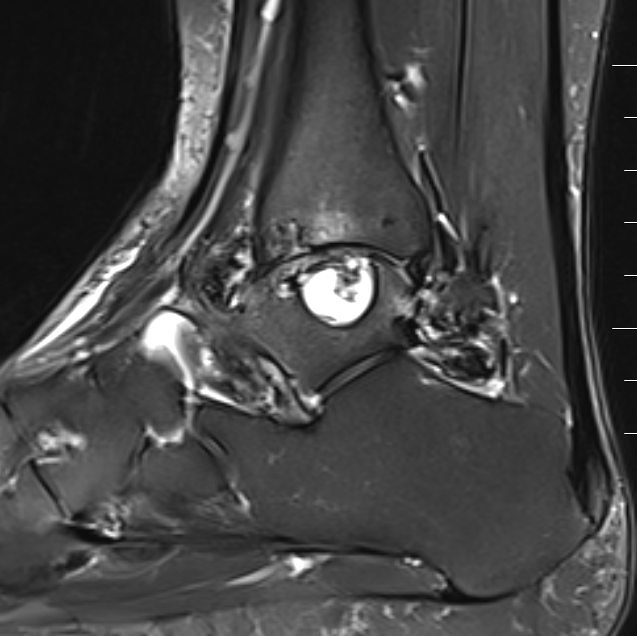

PVNS

Reclassified as same entity as soft tissue giant cell tumour

PVNS characteristically referred to an intra-articular lesion

Common around the ankle or midfoot

MRI - low signal on T1 and T2

PVNS anterolateral gutter ankle

PVNS with ankle joint / talus erosion